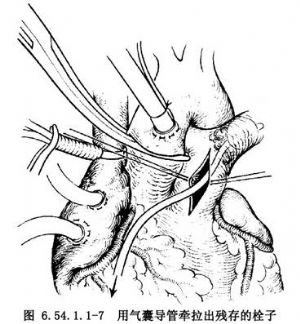

4.切开双侧胸膜腔,以手挤压肺脏以助深部栓子的排出(图6.54.1.1-6),也可用Fogarty气囊导管伸入双侧肺动脉牵拉出残存的栓子(图6.54.1.1-7)。切开右心房、右心室,检查有无存留在心腔内的栓子或附壁血栓、血块,予以取出,冲洗心腔。